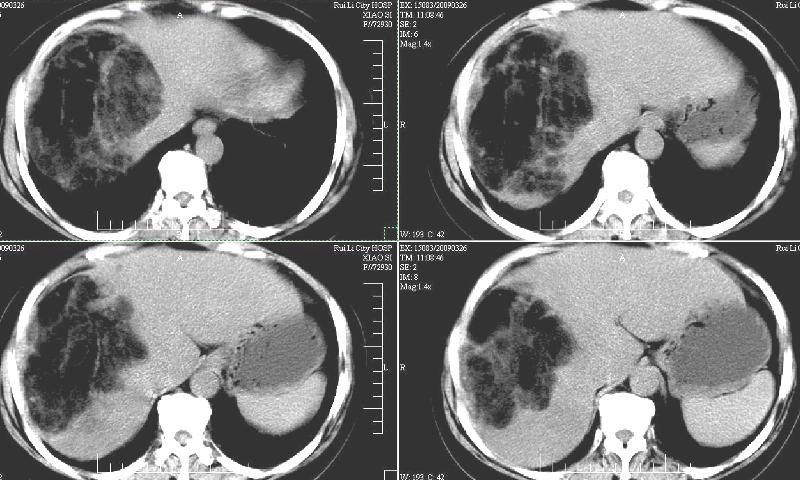

标题: CT19130:F,60岁。2008-10-17CT发现肝脏占位,现在复查! [打印本页]

标题: CT19130:F,60岁。2008-10-17CT发现肝脏占位,现在复查!

前次已经增强,所以这次没有增。ct:肝右叶平滑肌血管脂肪瘤治疗后复查,肿瘤大小同前或略有缩小。2、轻度脂肪肝。3、肝左叶小囊肿

支持楼主意见,肝右叶平滑肌血管脂肪瘤。